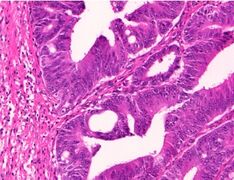

Adenocarcinoma is a malignant epithelial tumor, originating from superficial glandular epithelial cells lining the colon and rectum. It invades the wall, infiltrating the muscularis mucosae layer, the submucosa, and then the muscularis propria. Tumor cells describe irregular tubular structures, harboring pluristratification, multiple lumens, reduced stroma ("back to back" aspect). Sometimes, tumor cells are discohesive and secrete mucus, which invades the interstitium producing large pools of mucus. This occurs in mucinous adenocarcinoma, in which cells are poorly differentiated. If the mucus remains inside the tumor cell, it pushes the nucleus at the periphery, this occurs in "signet-ring cell." Depending on glandular architecture, cellular pleomorphism, and mucosecretion of the predominant pattern, adenocarcinoma may present three degrees of differentiation: well, moderately, and poorly differentiated.[5]

Cancer – Invasive adenocarcinoma (the most common type of colorectal cancer). The cancerous cells are seen in the center and at the bottom right of the image (blue). Near normal colon-lining cells are seen at the top right of the image.